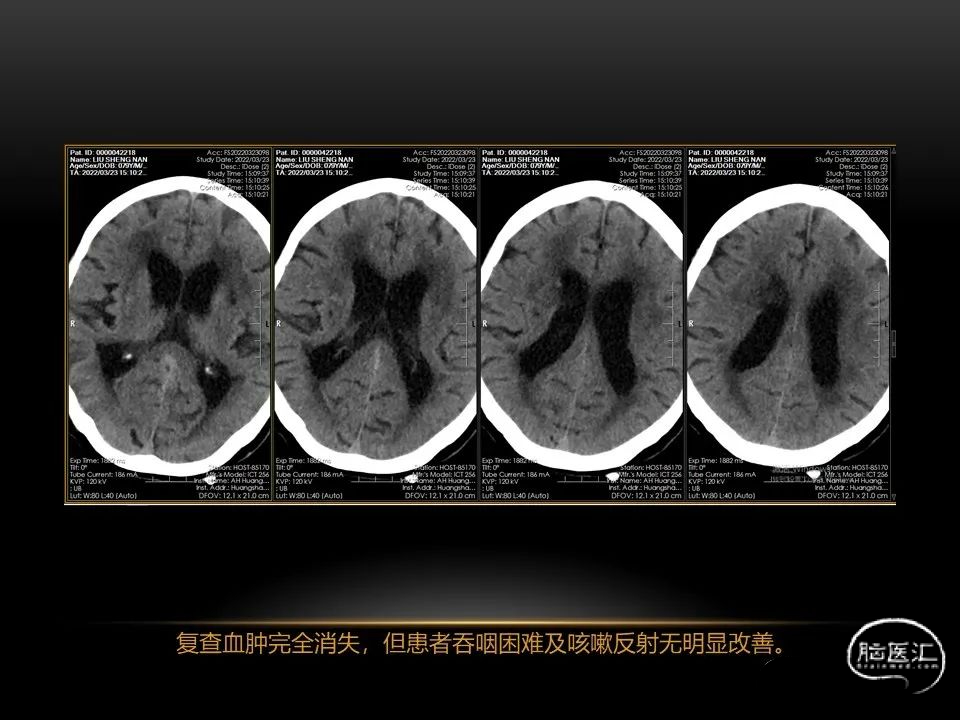

自发性脑出血不仅仅累及内囊后肢才会出现偏瘫及偏身感觉障碍,病变累及大脑脚或辐射冠同样有可能有类似症状和体征。内囊、辐射冠、大脑脚等结构之间是延续的,只是不同区域不同名称而已。定位诊断需要对解剖结构概念清晰,读片准确辨认,灵活掌握。

每位患者的病情都不完全一样,唯有通过不断积累、仔细分辨、细心总结,方能沉着应对,为患者造福。本人水平有限,有空就收集一些手头珍贵资料分析分析,总结总结,回味回味,总会发现很多不懂的,总会有新的收获。望老师和朋友们不吝赐教,给我留言交流心得。